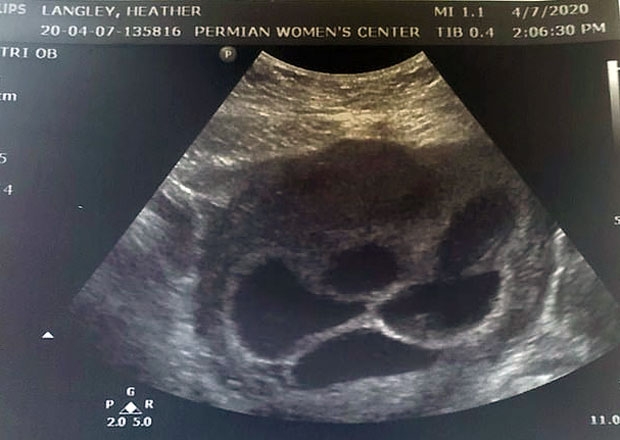

그만큼 희귀한 딸 다섯쌍둥이를 임신했다는 걸 알았을 때 랭리와 로드리게스는 엄청난 충격에 휩싸였다. 랭리는 “임신 6주째 다섯쌍둥이라는 걸 알았다. 두려웠다. 한꺼번에 5명을 어떻게 키우나 싶어 걱정이 앞섰다. 이름 고르기조차 벅찼다”고 말했다. 파트너인 로드리게스도 “농담하지 말라”며 믿을 수 없다는 반응을 보였다.